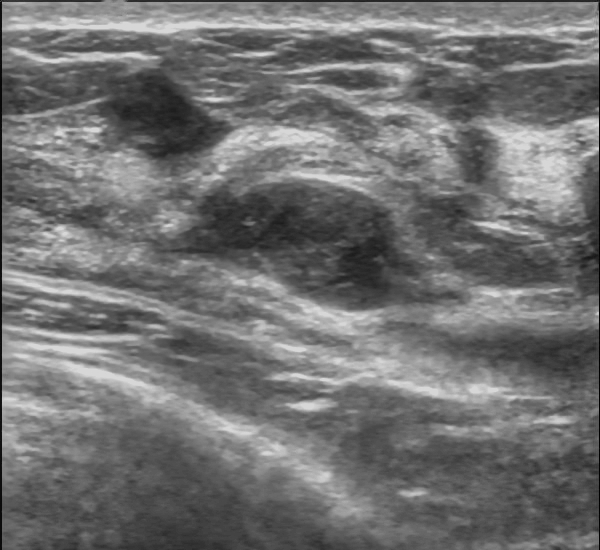

Phyllodes Tumor

Phyllodes tumor is a tumor with an overgrowth of the fibrous component that resembles a fibroadenoma.

The histology of Phyllodes tumor shows leaf-like projections.

Phyllodes tumor is most frequently observed in postmenopausal women and.

In some very rare instances, Phyllodes tumor may become malignant.